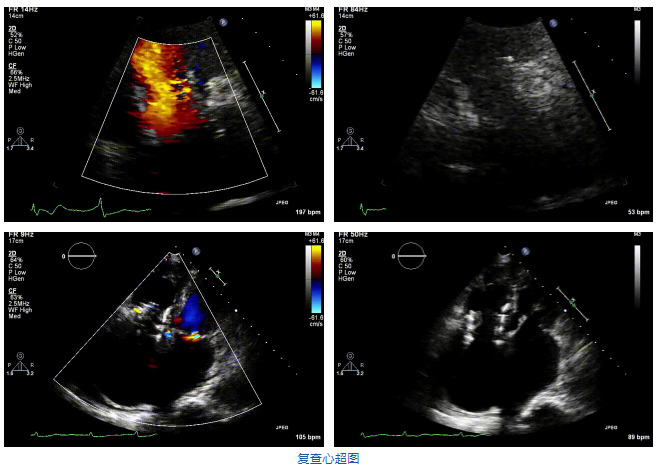

2021年12月7日,復(fù)旦大學(xué)附屬中山醫(yī)院葛均波院士團(tuán)隊(duì)完成的首批兩例LuX-Valve Plus經(jīng)血管三尖瓣置換患者順利出院,從患者入院至出院僅歷時(shí)一周時(shí)間,出院時(shí)患者狀態(tài)恢復(fù)良好,復(fù)查心超三尖瓣無(wú)反流。

結(jié)合術(shù)前CT評(píng)估結(jié)果,葛均波院士團(tuán)隊(duì)最終決定選用LuX-Valve Plus 50mm和55mm兩種型號(hào)的瓣膜,并于2021年11月30日順利完成LuX-Valve Plus經(jīng)血管三尖瓣置換術(shù),手術(shù)室即刻拔除氣管插管,術(shù)后第二天轉(zhuǎn)出心內(nèi)科監(jiān)護(hù)室,下床活動(dòng)。術(shù)后患者三尖瓣反流癥狀得到顯著改善,復(fù)查心超結(jié)果顯示人工三尖瓣瓣膜支架固定穩(wěn)定,瓣葉關(guān)閉形態(tài)未見(jiàn)異常,未見(jiàn)明顯反流。

在本次救治性臨床研究中,治療的兩例患者病因不同,解剖結(jié)構(gòu)復(fù)雜,均為極重度三尖瓣反流,手術(shù)最終都順利植入了LuX-Valve Plus三尖瓣人工瓣膜。術(shù)后超聲顯示瓣膜支架固定穩(wěn)定,反流癥狀顯著改善,取得了良好臨床治療效果。